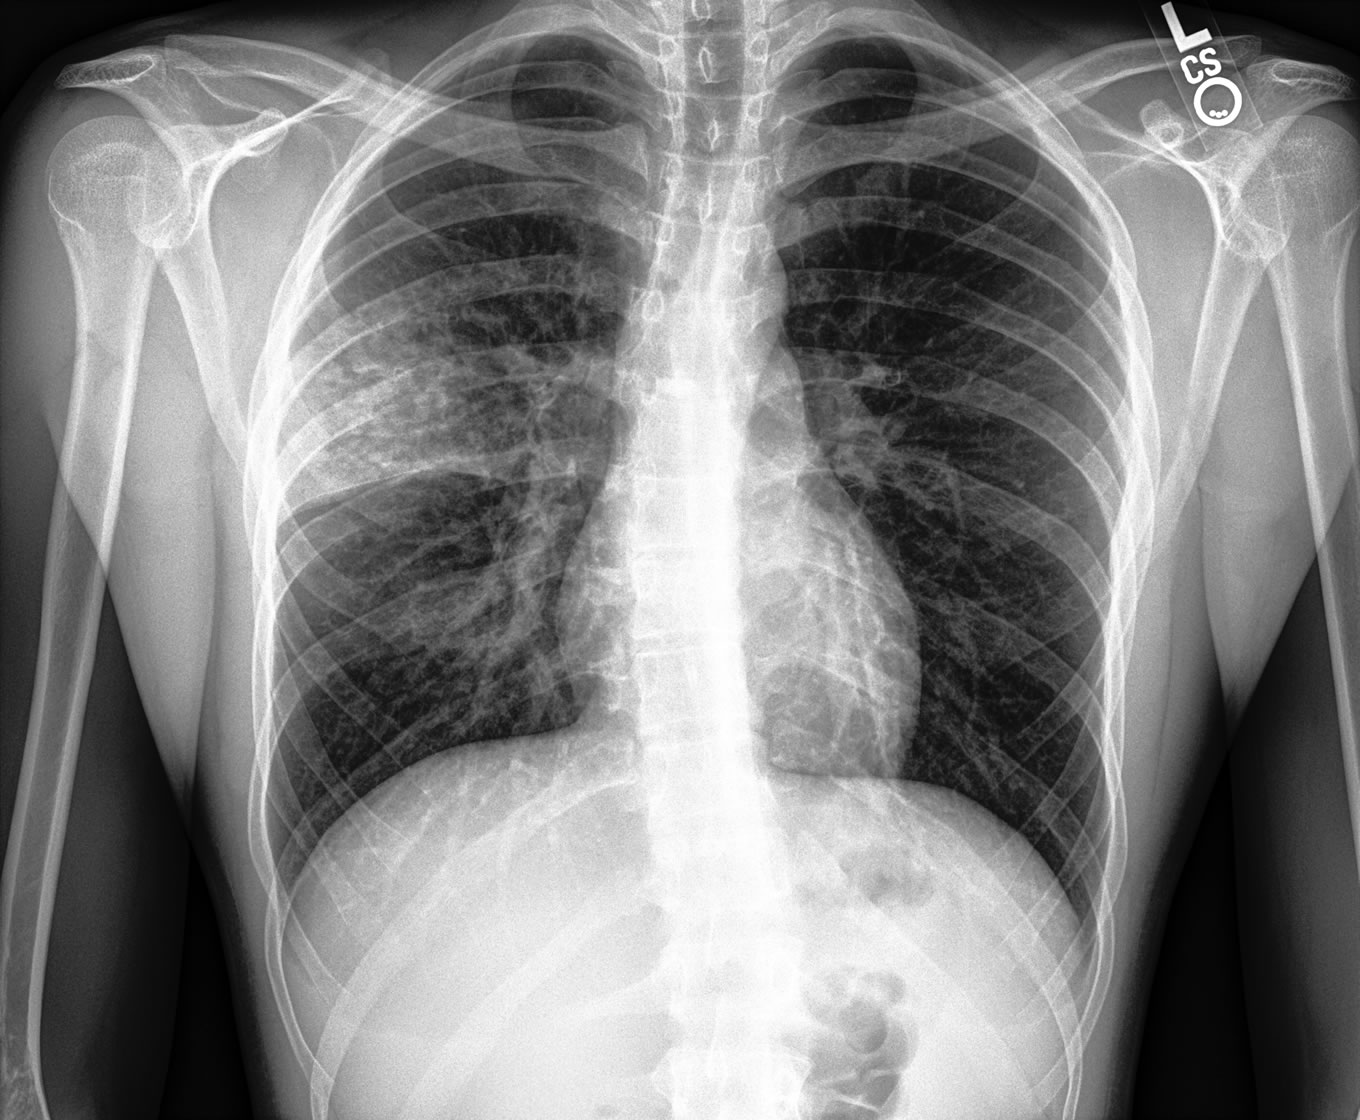

Imagen original

La radiografia es consultada al PACS de forma automática